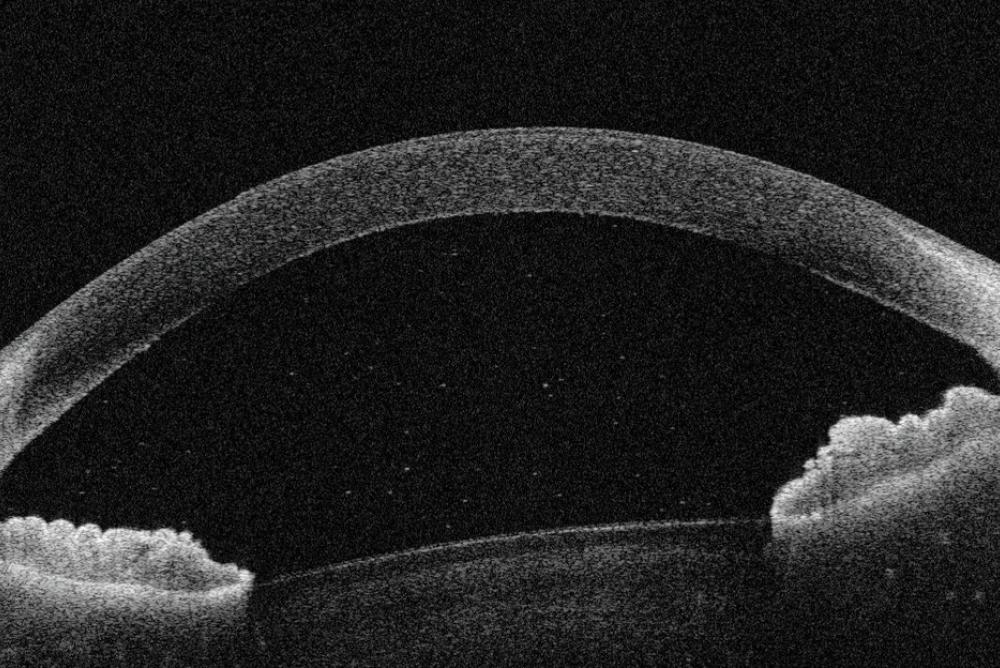

This scan image is taken from a separate Uveitis research project 'Eye on Eyes' led by Dr Lola Solebo, Consultant Paediatric Ophthalmologist, GOSH

© This scan image is taken from a separate Uveitis research project 'Eye on Eyes' led by Dr Lola Solebo, Consultant Paediatric Ophthalmologist, GOSH